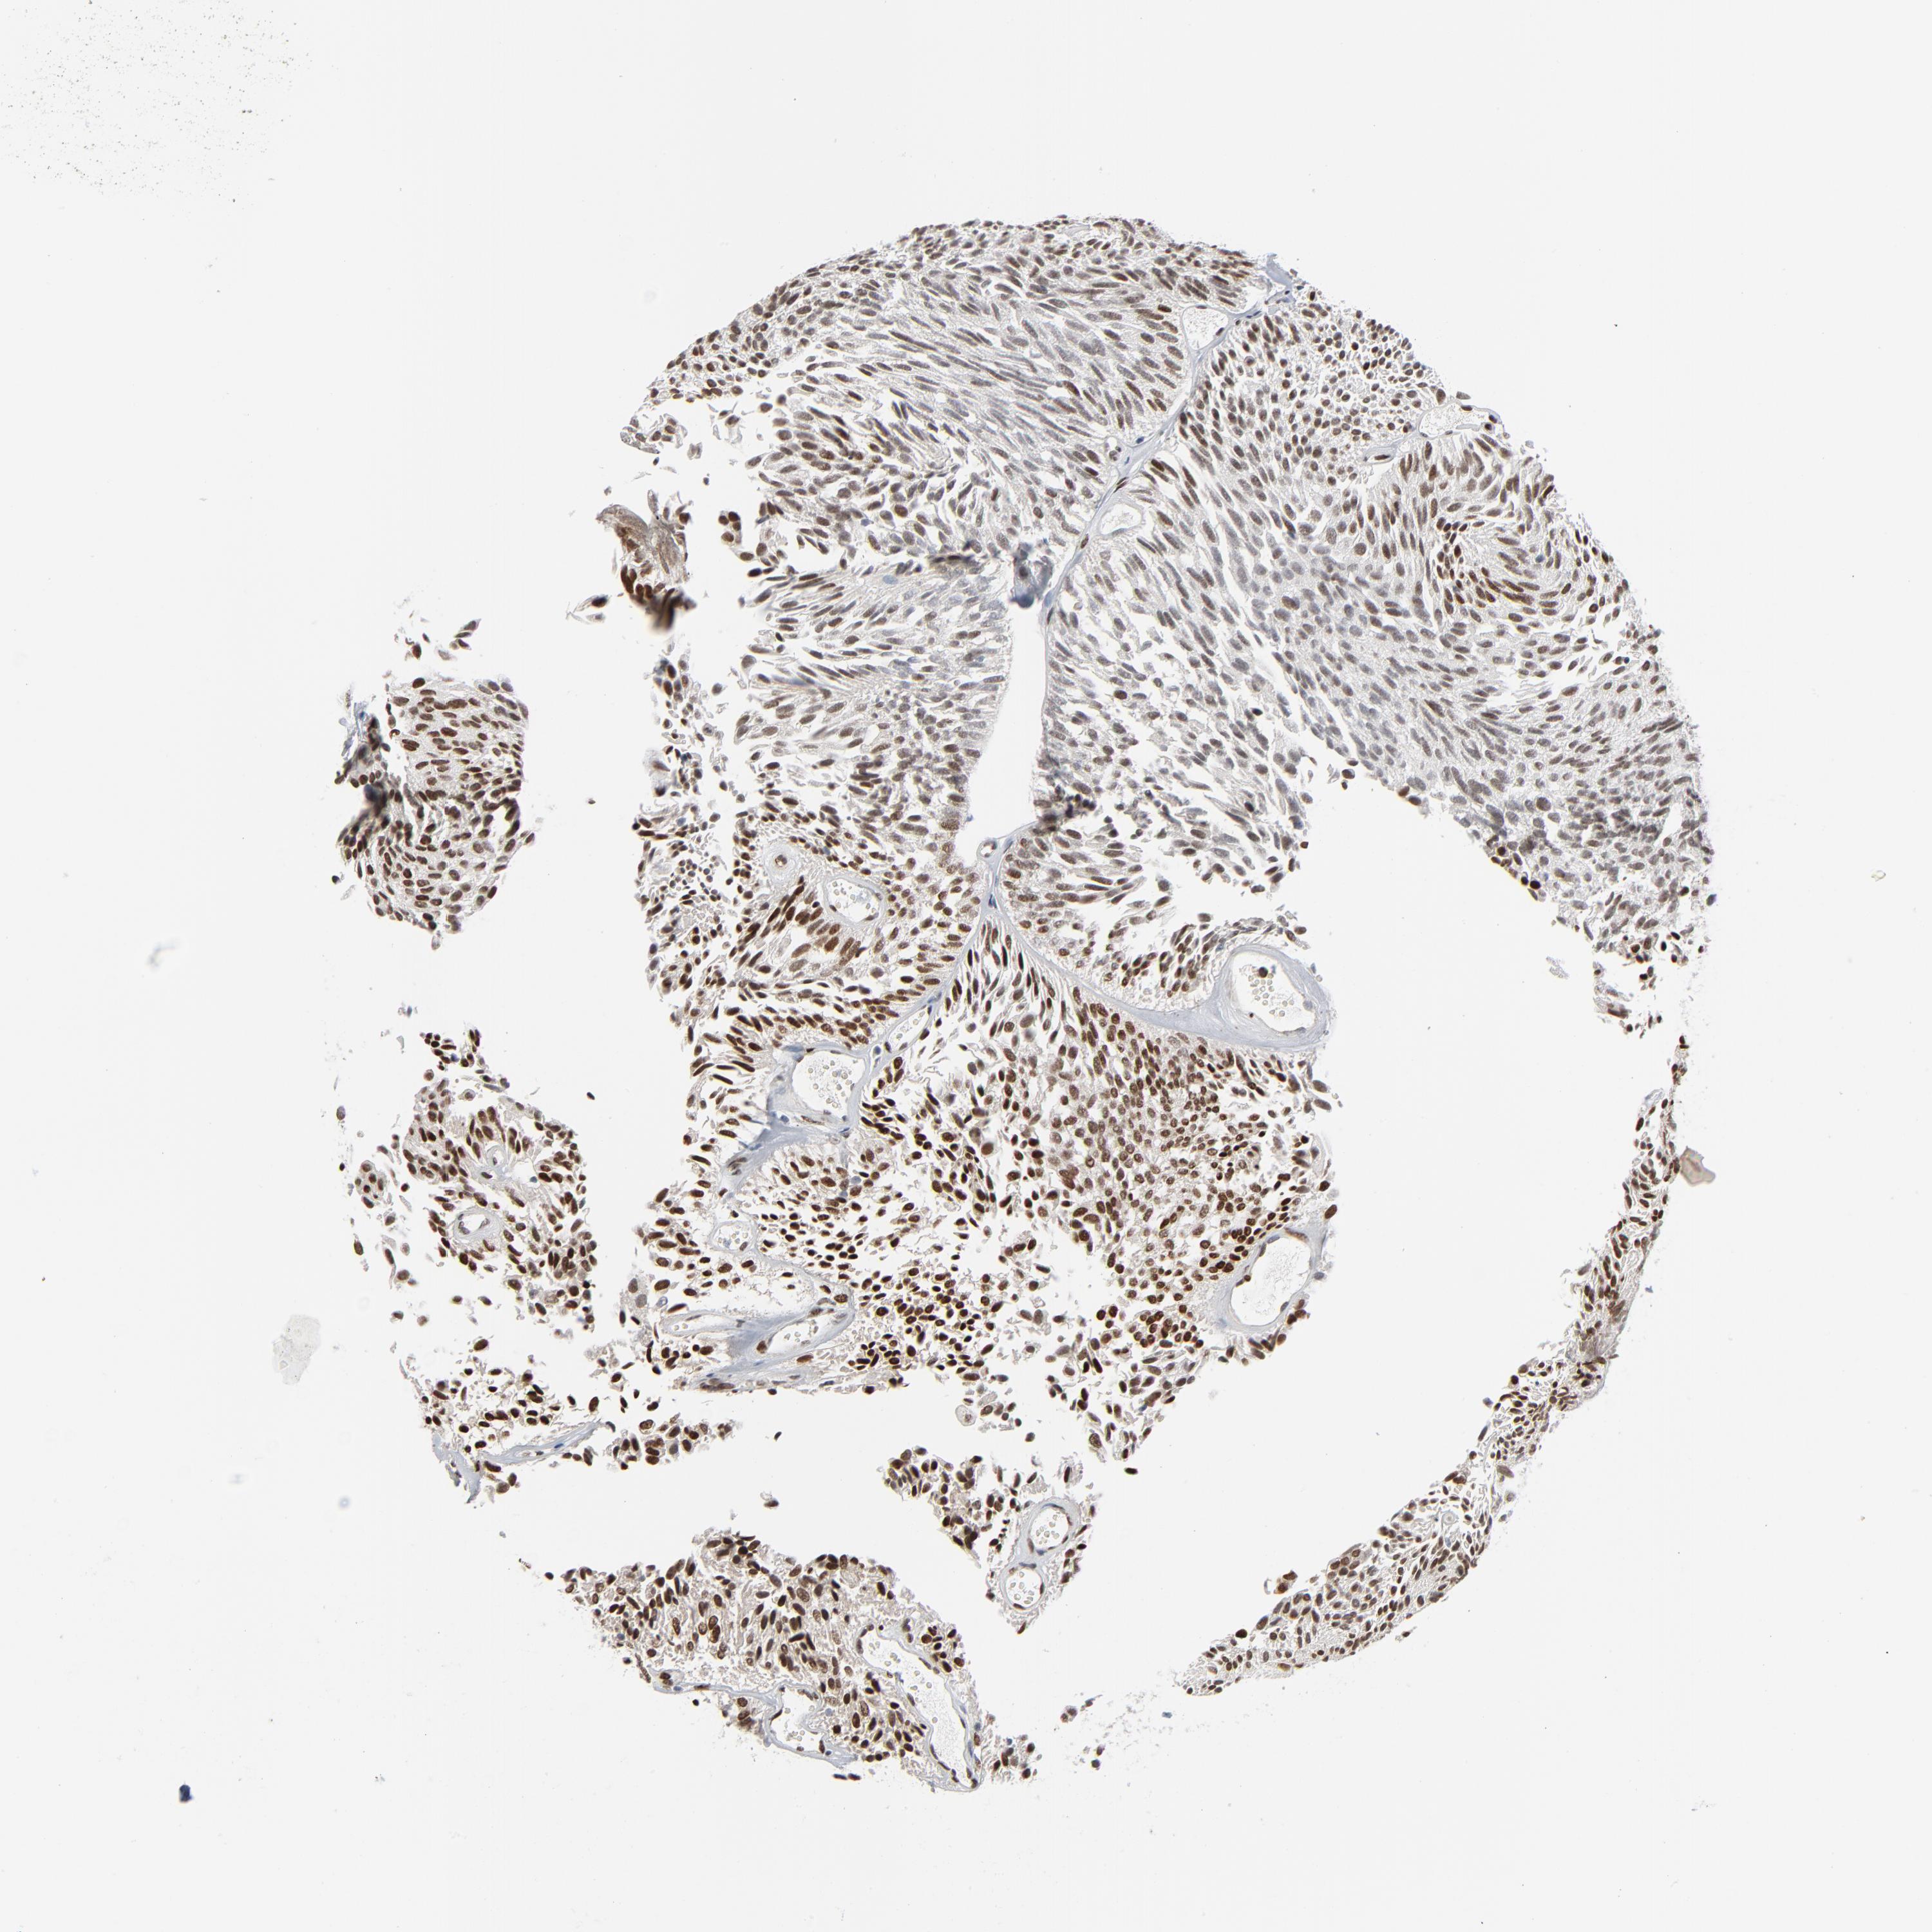

UROTHELIAL CANCER - Protein expressioni

A mouse-over function shows sample information and annotation data. Click on an image to view it in a full screen mode. Samples can be filtered based on level of antibody staining by selecting one or several of the following categories: high, medium, low and not detected. The assay and annotation is described here.

Antibody stainingi

Antibody staining in the annotated cell types in the current human tissue is reported as not detected, low, medium, or high, based on conventional immunohistochemistry profiling in selected tissues. This score is based on the combination of the staining intensity and fraction of stained cells.

Each image is clickable and will lead to virtual microscopy that enables deeper exploration of all samples and also displays staining intensity scores, fraction scores and subcellular localization as well as patient and tissue information for each sample.

Antibody HPA003277

Antibody HPA003317

Staining

High

Medium

Low

Not detected

Intensity

Strong

Moderate

Weak

Negative

Quantity

>75%

75%-25%

<25%

None

Location

Nuclear

Cytoplasmic/membranous

Cytoplasmic/membranous,nuclear

Urothelial carcinoma, High grade